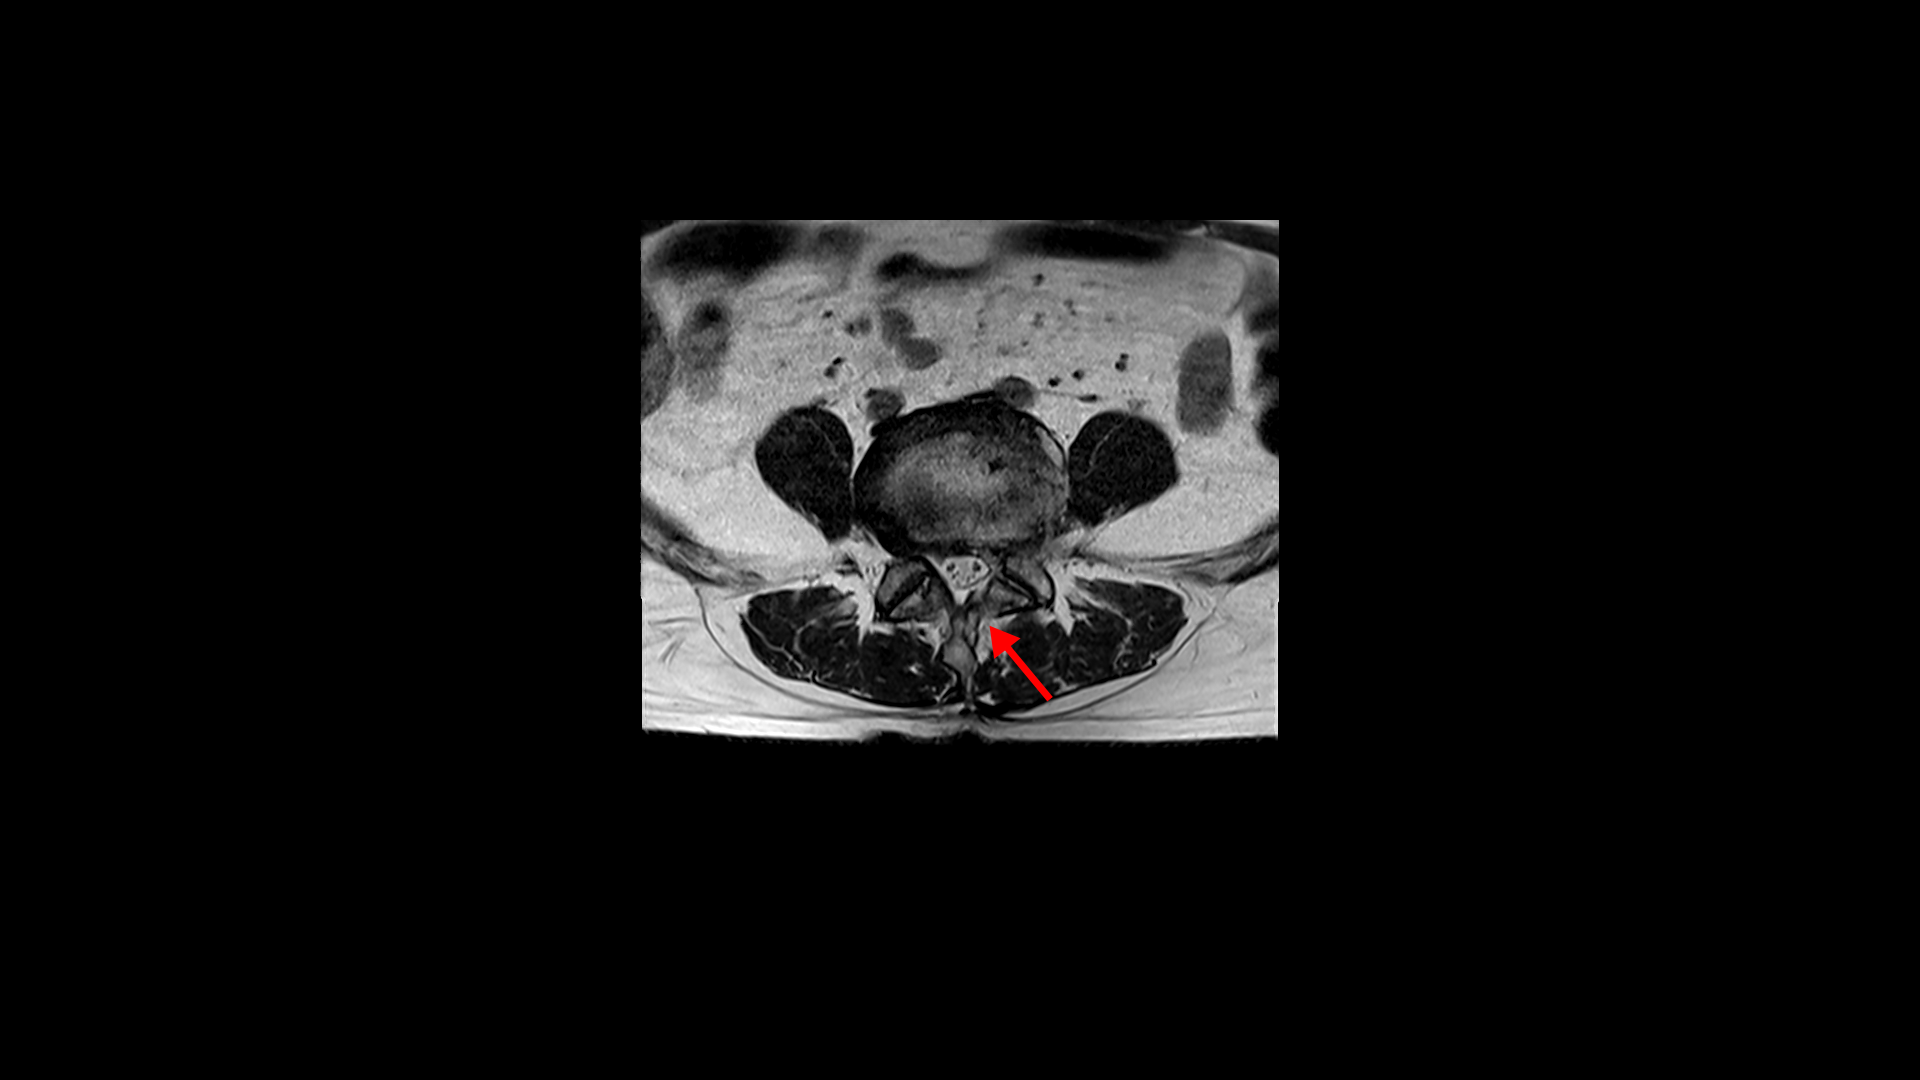

3번 4번은 왼쪽 중앙으로 밀려나와있고

4번 5번은 왼쪽 신경이 빠져나가는 추간공이 뼈가 자라면서 좁아져 추간공협착이 있습니다.

또 왼쪽 후궁에는 과거에 받은 수술의 흔적도 보입니다.